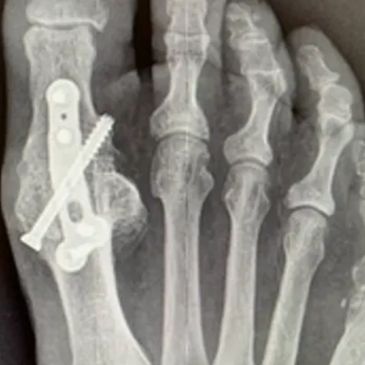

Bunion(hallux valgus) surgery has the following aims:

Correct the deformity of the big toe and first metatarsal bone.

Relieve pain and pressure.

Improve function and make it easier to wear normal shoes.

Reduce the risk of long-term problems such as arthritis.

Rheumatoid forefoot reconstruction corrects forefoot deformity in rheumatoid arthritis to relieve pain and improve walking function. It restores alignment and reduces pressure points when non-surgical treatments no longer help.

A bunionette (tailor’s bunion) causes a painful bump on the outside of the foot that rubs in shoes. Surgical correction reduces the prominence and restores comfort when conservative measures fail.